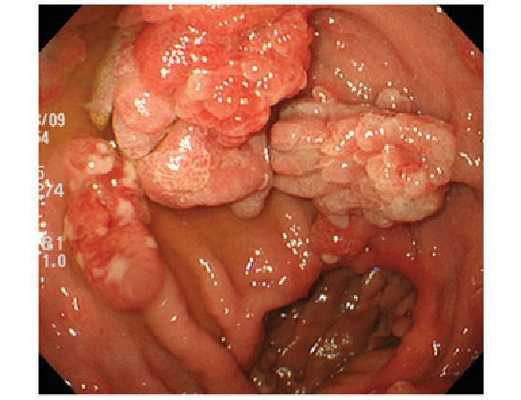

В ряде случаев полипы удается выявить уже на стадии ректального осмотра. Для оценки состояния нижних отделов кишечника и определения выраженности семейного полипоза толстой кишки осуществляют ректороманоскопию. Затем проводят колоноскопию. В процессе эндоскопических исследований обращают внимание на более крупные вишневые либо ярко-красные узлы с рыхлой либо дольчатой поверхностью (ворсинчатые полипы), поскольку для таких опухолей характерна повышенная вероятность озлокачествления.

Полипы при диффузном полипозе имеют разные размеры и строение: одни небольшого размера, до одного сантиметра, имеют преимущественно железистую структуру, другие больше сантиметра в диаметре, с ворсинчатой поверхностью и дольчатой структурой. Располагаться полипы могут на широкой основе или на ножке, часто сливаются, в местах слияния практически отсутствует нормальная слизистая оболочка. Малигнизацию в аденоматозных полипах выявляют приблизительно в 30% случаев. Ворсинчатые полипы переходят в злокачественную форму в два раза чаще. Признаком малигнизации является увеличение полипа, неровность его поверхности, изменение цвета, появление изъязвлений. Считается, что возникновение раковых опухолей при диффузном полипозе - это только вопрос времени.

- Ворсинчатые (папиллярные) полипы толстой кишки. Выявляются у 14% пациентов. Представляют собой узлы или стелющиеся образования, имеющие насыщенный красный цвет из-за большого количества кровеносных сосудов. Могут достигать 3-5 и более см. Ворсинчатые полипы часто изъязвляются и кровоточат, возможно образование участков некроза. Обладают высокой склонностью к малигнизации.